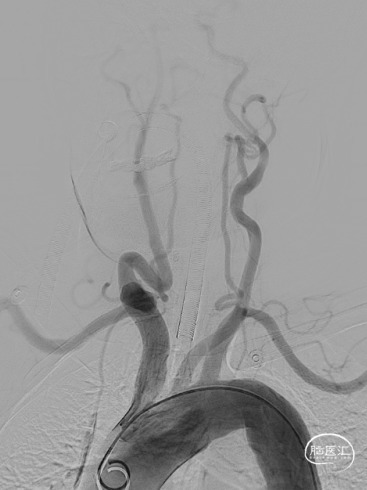

术前造影

造影显示Ⅱ型主动脉弓,RCCA起始段Z字型反向迂曲;RMCA:开口闭塞,TICI分级0级,远端由RACA经皮层支少量代偿,ASITN分级2级。